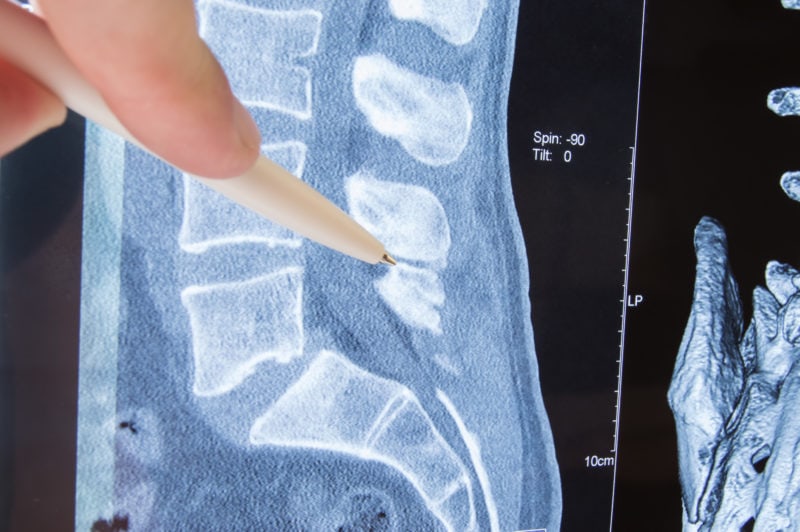

What To Expect From Spinal Stenosis Surgery . — recovery from spinal stenosis surgery can be a challenging process if significant back pain and activity limitations still exist several weeks after the surgery was performed. — surgical treatments for spinal stenosis include laminectomy, discectomy, and spinal fusion. — throughout the first few weeks after your cervical spinal stenosis surgery, you can expect your mobility to increase and your pain and swelling to decrease. A doctor may recommend surgery for spinal stenosis in severe cases or if nonsurgical methods do not. Spinal stenosis surgery is a procedure to create more space in the. After two to four weeks, most patients return to work or school and find that they no longer need their prescribed pain medications. — this surgery is done only on spinal bones in the neck. — spinal stenosis surgery helps to reopen your spinal canal, the channel in your backbone that houses your spinal. It makes the space within the spinal canal bigger by creating. — what to expect. It is important to follow all instructions from your surgeon and physical therapist to promote optimal healing and recovery for the best possible outcome.